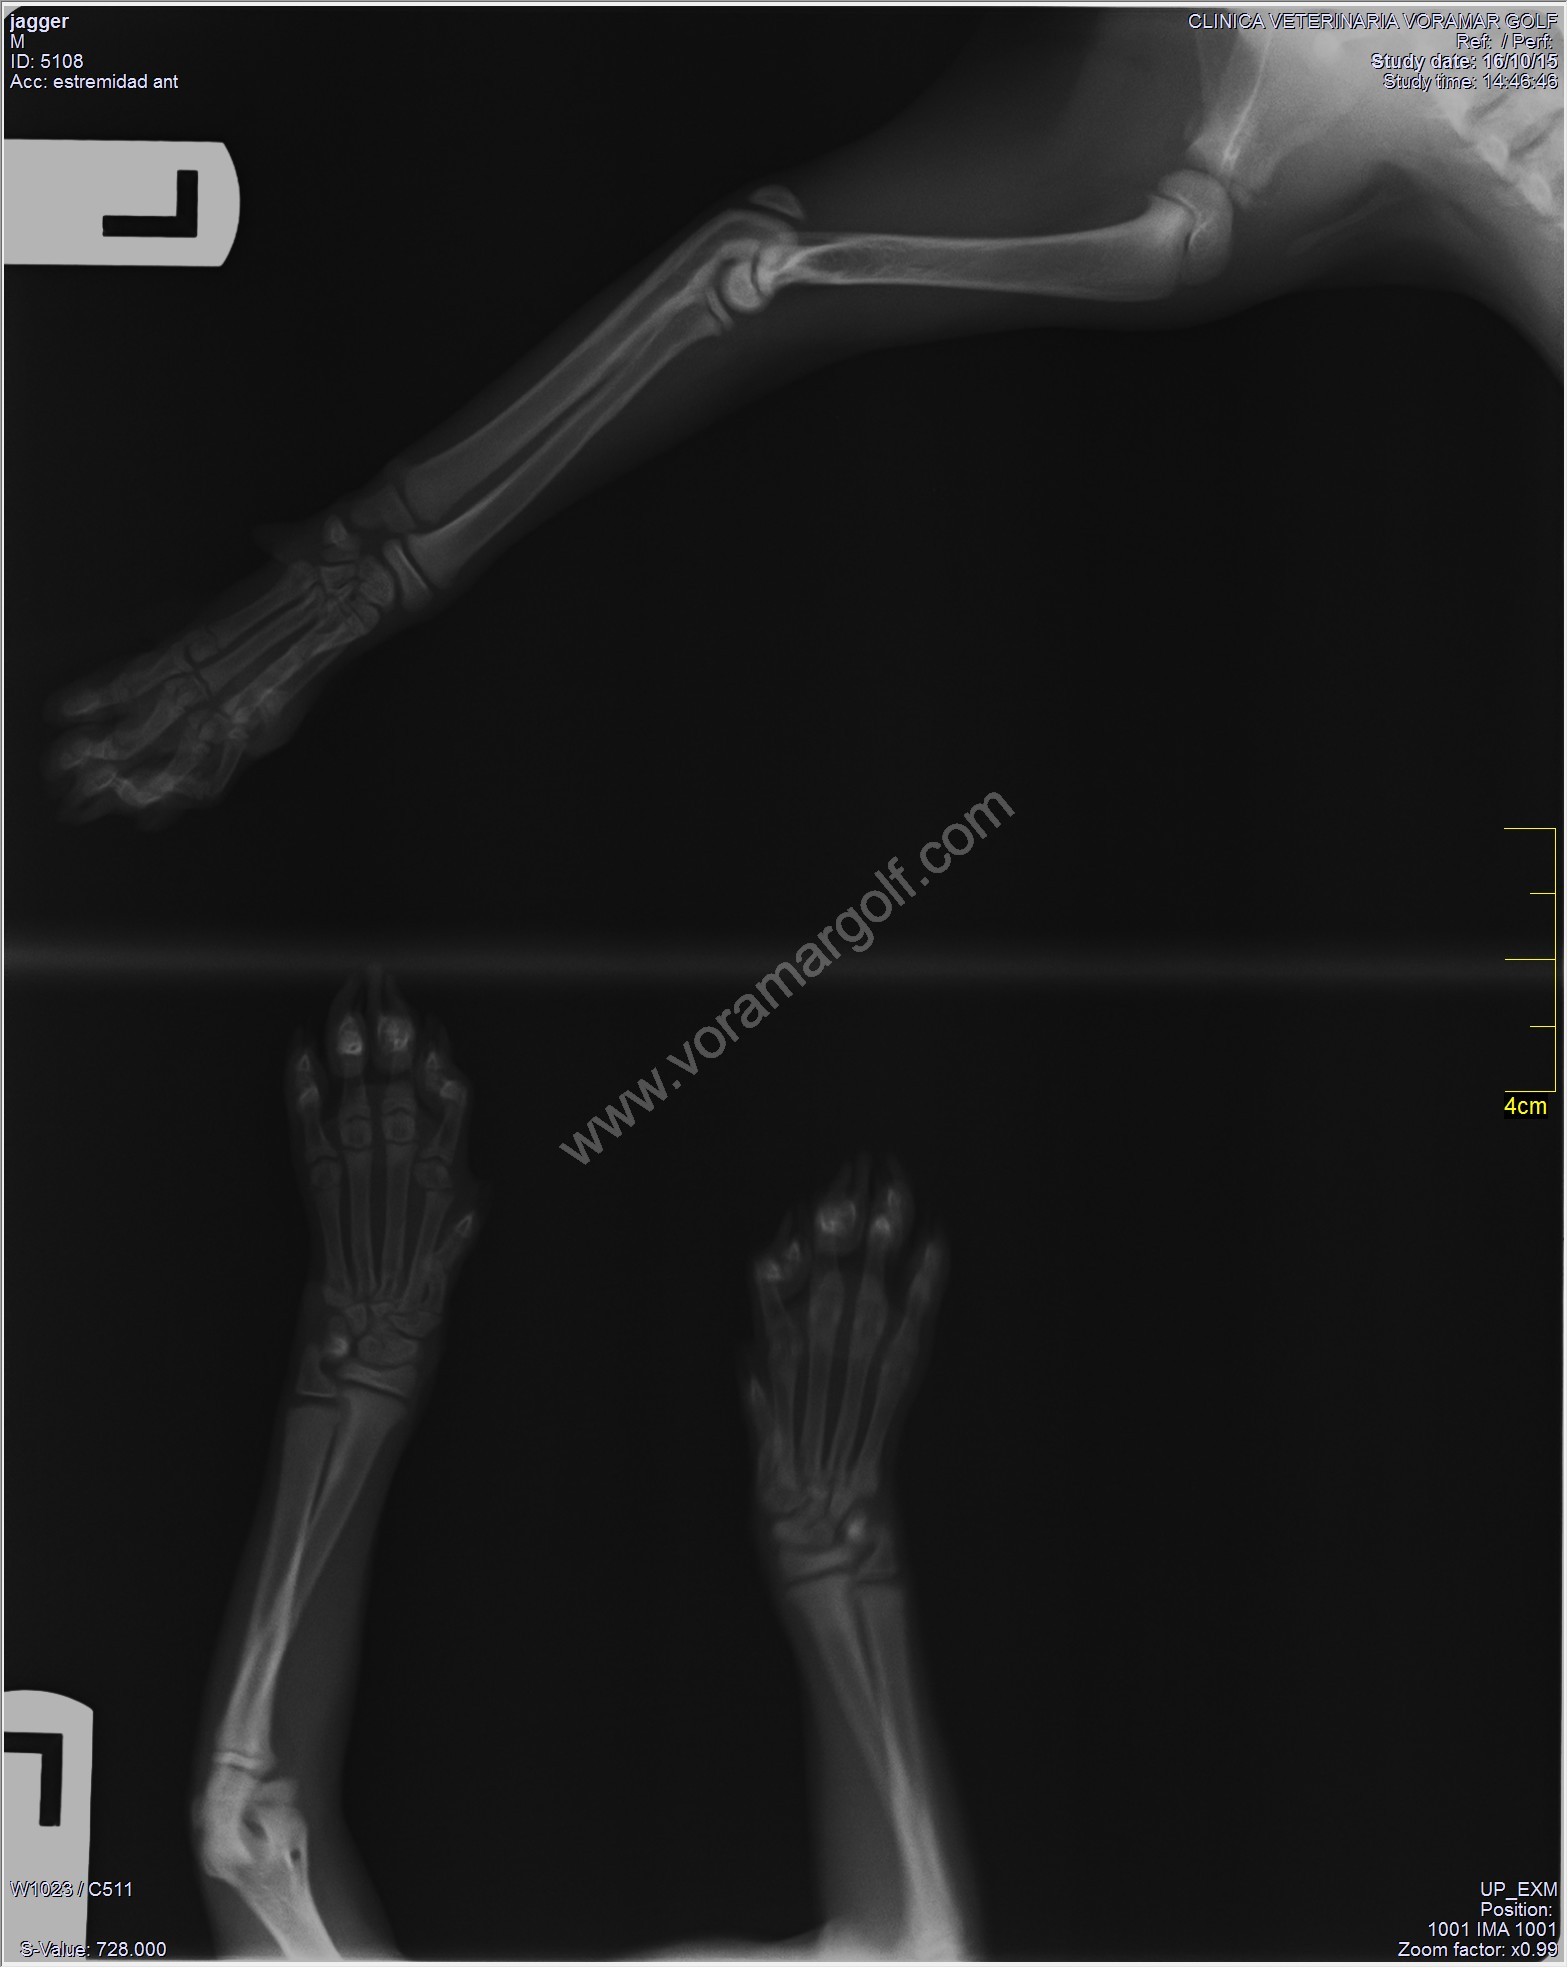

Este es Jagger, un gatito de 2 meses que nos ha vistado hoy. Jagger cojeaba de su mano, y sus dueños no habían observado que se hubiera dado ningún golpe.

Gracias a la Radiología Digital podemos diagnosticar con precisión lo que tiene Jagger.

En ella podemos ver una fractura de el segundo metacarpiano de su mano izquierda.